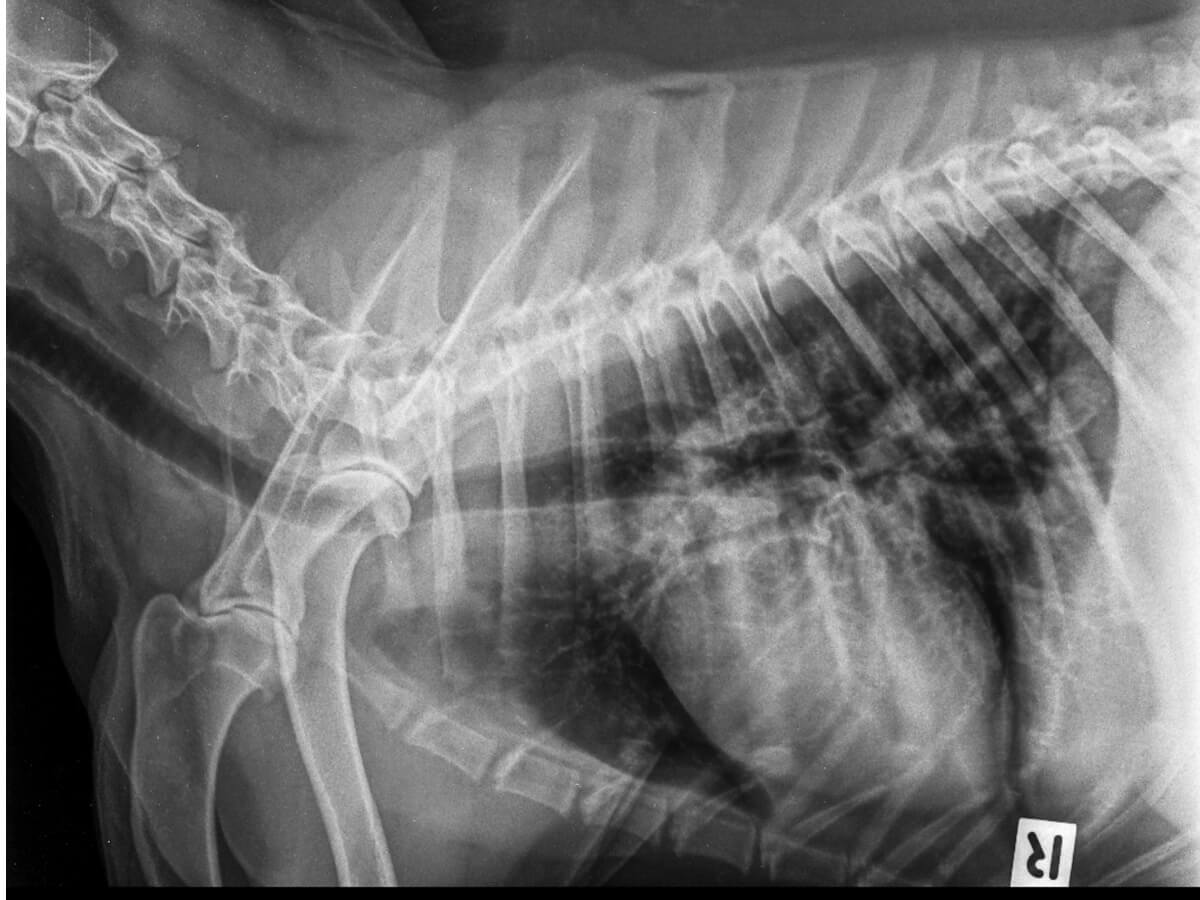

Placas radiográficas

El uso de la radiología permite observar la presencia de aire más allá de los pulmones. Se considera una prueba precisa para el diagnóstico de neumotórax en perros, pero no para identificar su causa.

Se recomienda realizar la toma de las placas en tres proyecciones, pues esto permitirá visualizar toda anormalidad en las estructuras dentro de la cavidad torácica. Debe hacerse un manejo con cautela, para evitar aumentar el estrés del paciente.